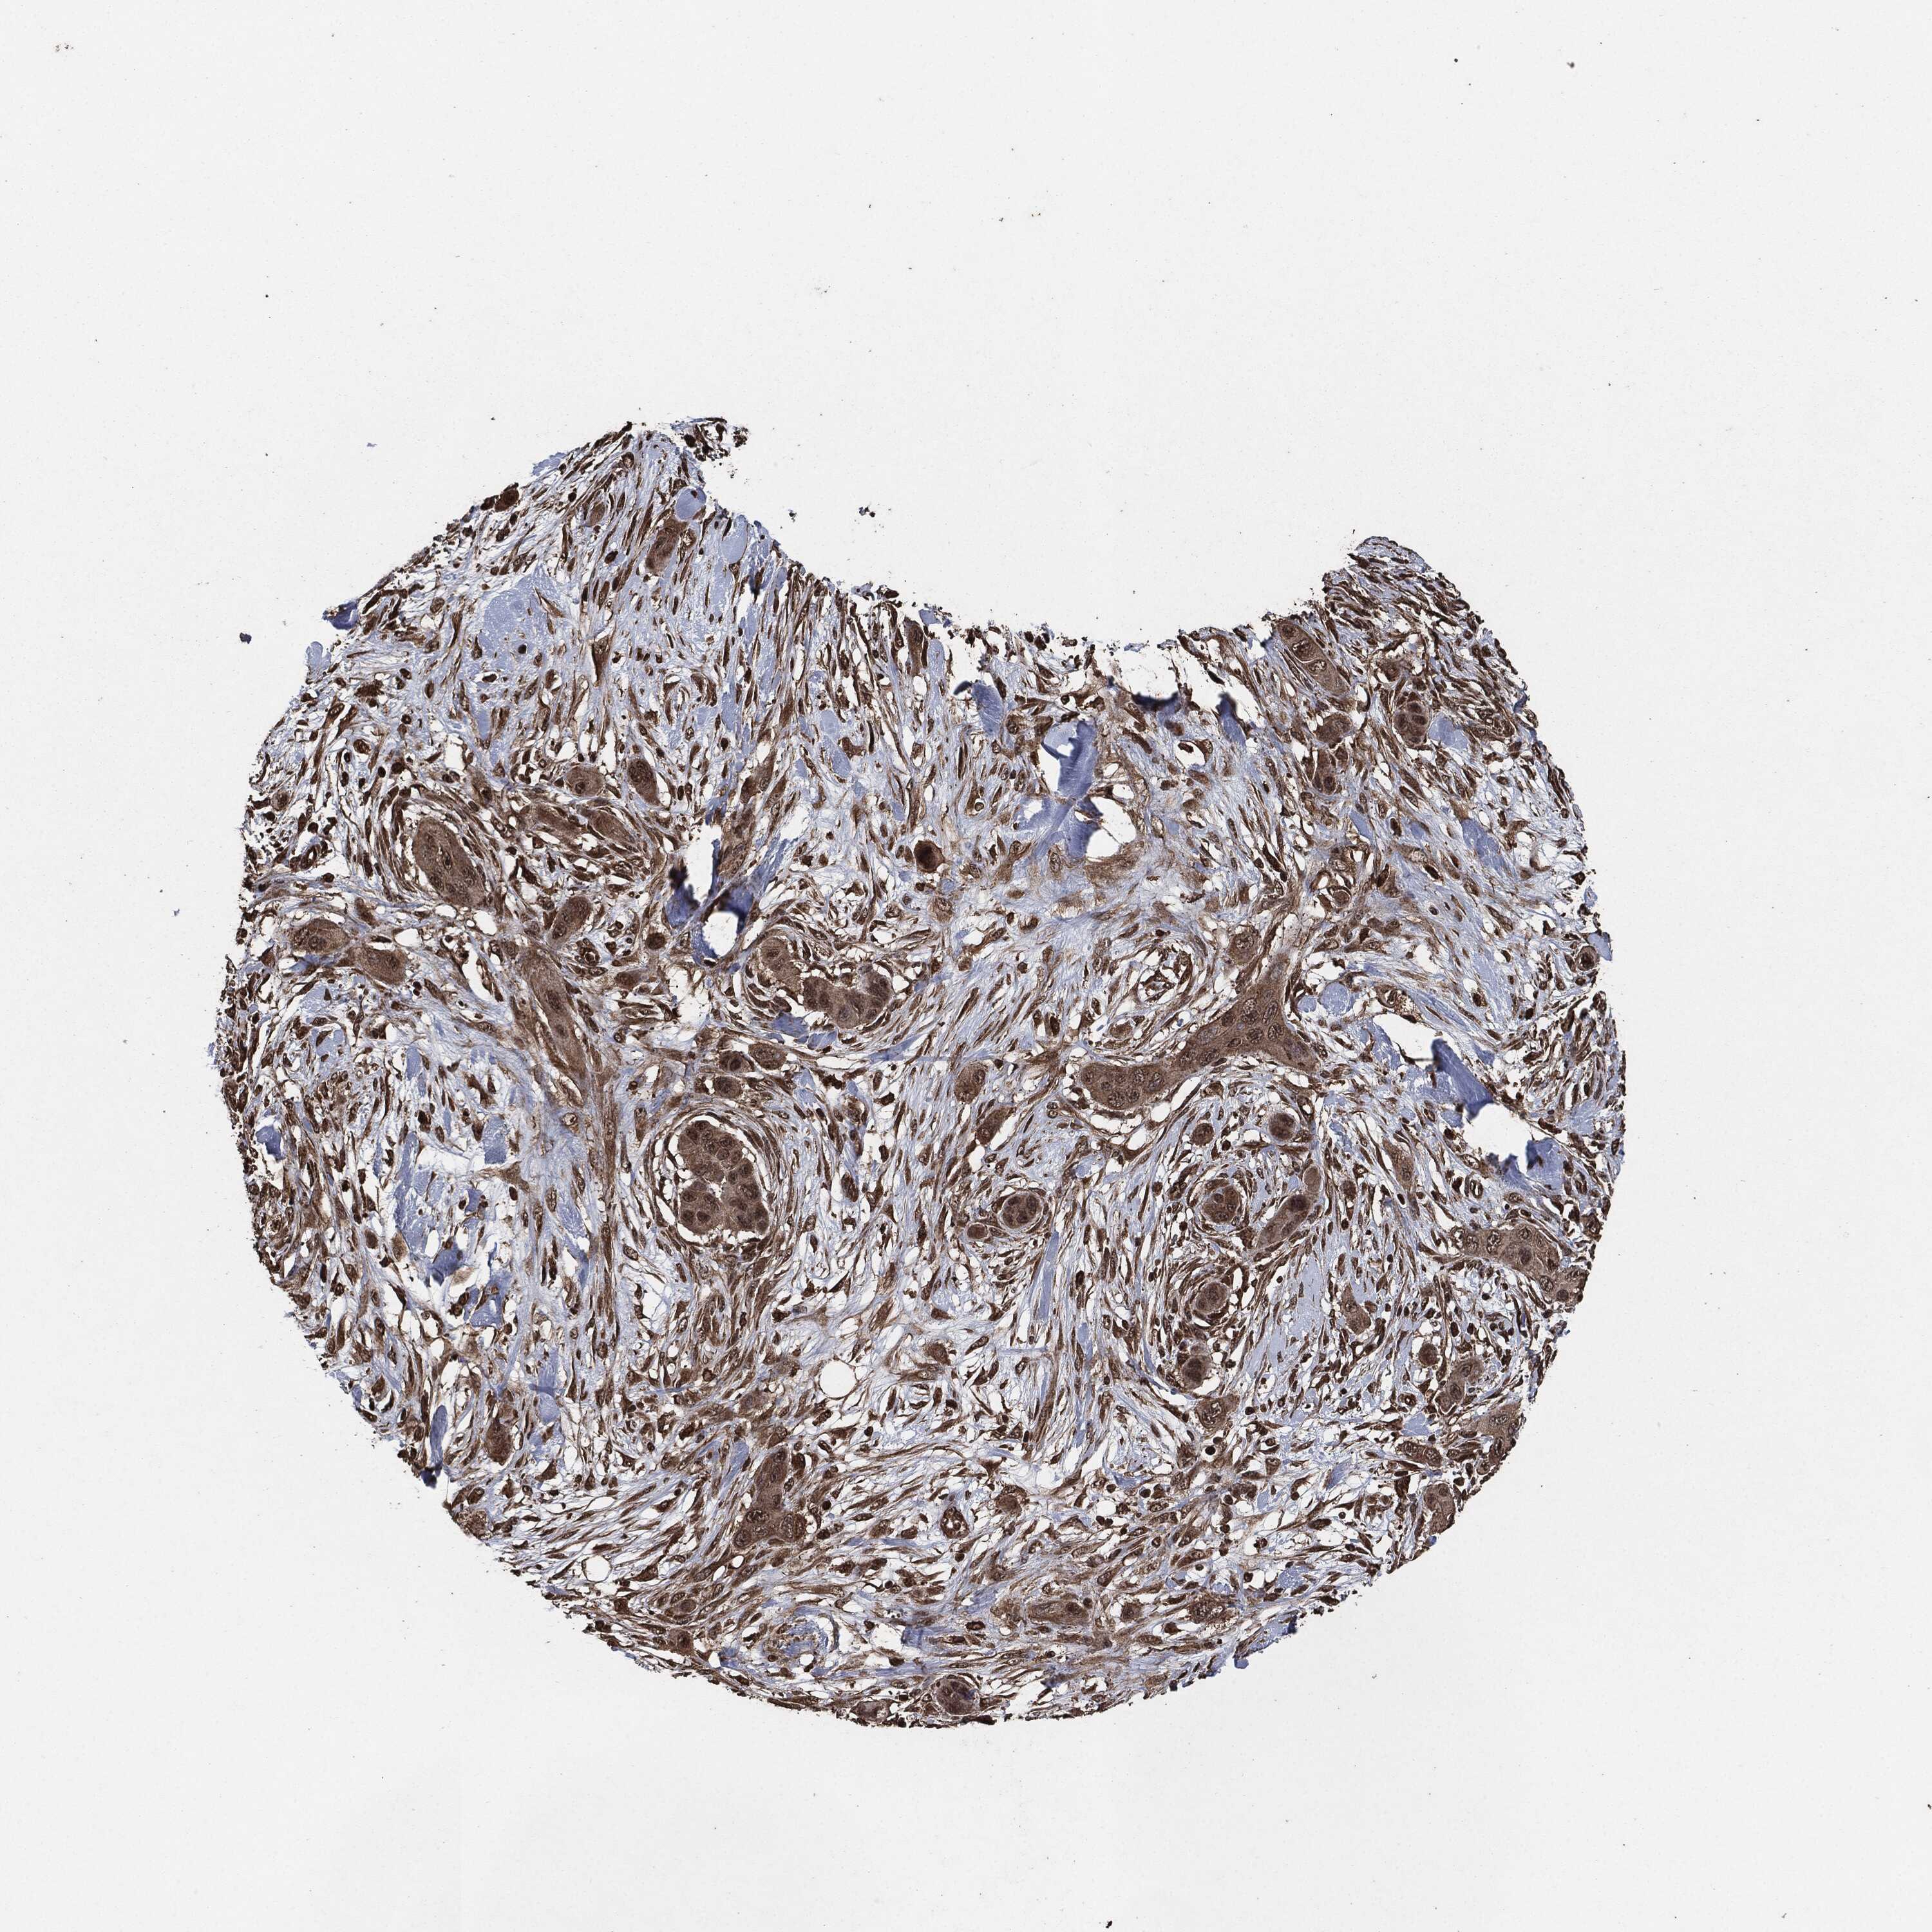

SKIN CANCER - Protein expressioni

A mouse-over function shows sample information and annotation data. Click on an image to view it in a full screen mode. Samples can be filtered based on level of antibody staining by selecting one or several of the following categories: high, medium, low and not detected. The assay and annotation is described here.

Antibody stainingi

Antibody staining in the annotated cell types in the current human tissue is reported as not detected, low, medium, or high, based on conventional immunohistochemistry profiling in selected tissues. This score is based on the combination of the staining intensity and fraction of stained cells.

Each image is clickable and will lead to virtual microscopy that enables deeper exploration of all samples and also displays staining intensity scores, fraction scores and subcellular localization as well as patient and tissue information for each sample.

Basal cell carcinoma

Squamous cell carcinoma, metastatic, NOS